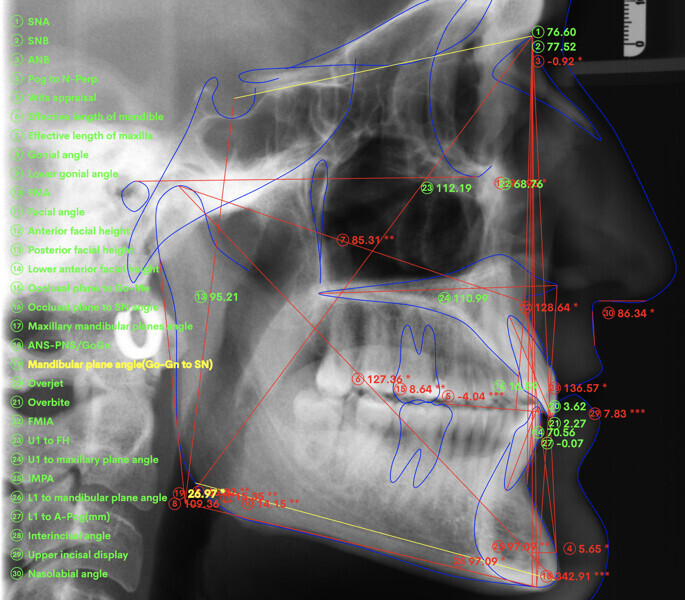

Le motif principal de consultation de ce patient âgé de 37 ans, était de rétablir l’alignement des dents antérieures sur les deux arcades. L’analyse faciale a indiqué une face courte avec un profil plat, mais une projection normale du menton (Figs. 9–12), et l’examen clinique a révélé une classe squelettique de type I (angle ANB = 0,89°) et une malocclusion de classe I avec supraclusion sévère (près de 100 %), une courbe de Spee très prononcée, un torque normal de l’incisive centrale supérieure (Ui-FH = 110°), un encombrement dentaire léger sur l’arcade maxillaire et modéré sur l’arcade mandibulaire (Figs. 13–18). Chez ce patient, les composantes de la supraclusion correspondaient à une dysmorphie squelettique grave correspondant à une hypodivergence (FMA = 14,24°), avec une inclinaison normale des incisives supérieures et inférieures et un angle goniaque réduit (110,46°). L’analyse du cliché céphalométrique indiquait une hauteur réduite de l’étage inférieur de la face associée à l’hypodivergence (Fig. 19). La seule option de traitement envisagée était un traitement orthodontique par aligneurs avec tous les éléments auxiliaires décrits (rampes d’occlusion, zones de pression, nivellement de la courbe de Spee dans les trois dimensions, élastiques de classe II et puissants contacts occlusaux) afin de corriger la supraclusion.